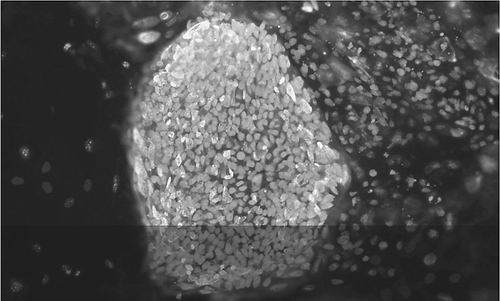

衍生自Ⅰ型糖尿病患者的胚胎干细胞。图片来源:BJARKI JOHANNESSON, NYSCF

另外,4月28日在线发表于《自然》杂志的研究报告称,美国纽约干细胞基金会(NYSCF)研究所的Dieter Egli和同事得到了更进一步的成果。研究人员利用一位32岁患有Ⅰ型糖尿病的女性的细胞制造出胚胎干细胞。然后,科学家促使这些胚胎干细胞变成患者体内丢失不见的胰岛素分泌细胞。